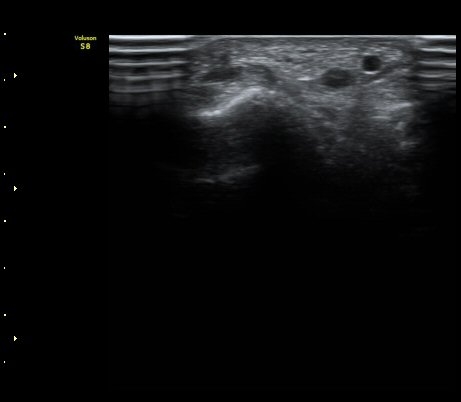

[ÆÈ²ÞÄ¡] ¿»ó ÈÄ ¹ß»ýÇÑ ¿ä°ñ½Å°æ ¸»´Ü °¨°¢½Å°æ ºÐÁö º´Áõ